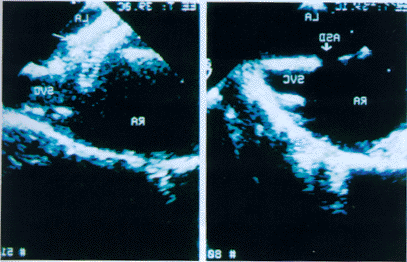

左图箭头示房间隔缺损;右图箭头示Amplatzer闭合器修补术后的超声图像

图1 Amplatzer闭合器修补房间隔缺损前(左图)和后(右图)经食管超声显像

超声监测 所有患者均在超声心动图监测下行经右心导管Amplatzer闭合器修补房间隔缺损。术中7例行经食管超声心动图监测,1例行经胸超声心动图监测。先经超声心动图测量房间隔缺损的大小以及残端的长度。嗣后于右下肢股静脉穿刺插入球囊导管至房间隔缺损处,经球囊注水测房间隔缺损大小,选择相应型号的Amplatzer闭合器至左房。超声心动图监测闭合器与房间隔的相对位置,使闭合器的第一个伞撑开后,伞的平面与房间隔平行,然后撑开第二个伞,使之正好夹住缺损(图1)。最后经右心造影及彩色血流显像证实无残余分流,且闭合器不影响二尖瓣的形态活动后手术告结束。患者术后服用抗生素及肠溶阿司匹林。第二天复查经胸超声心动图。